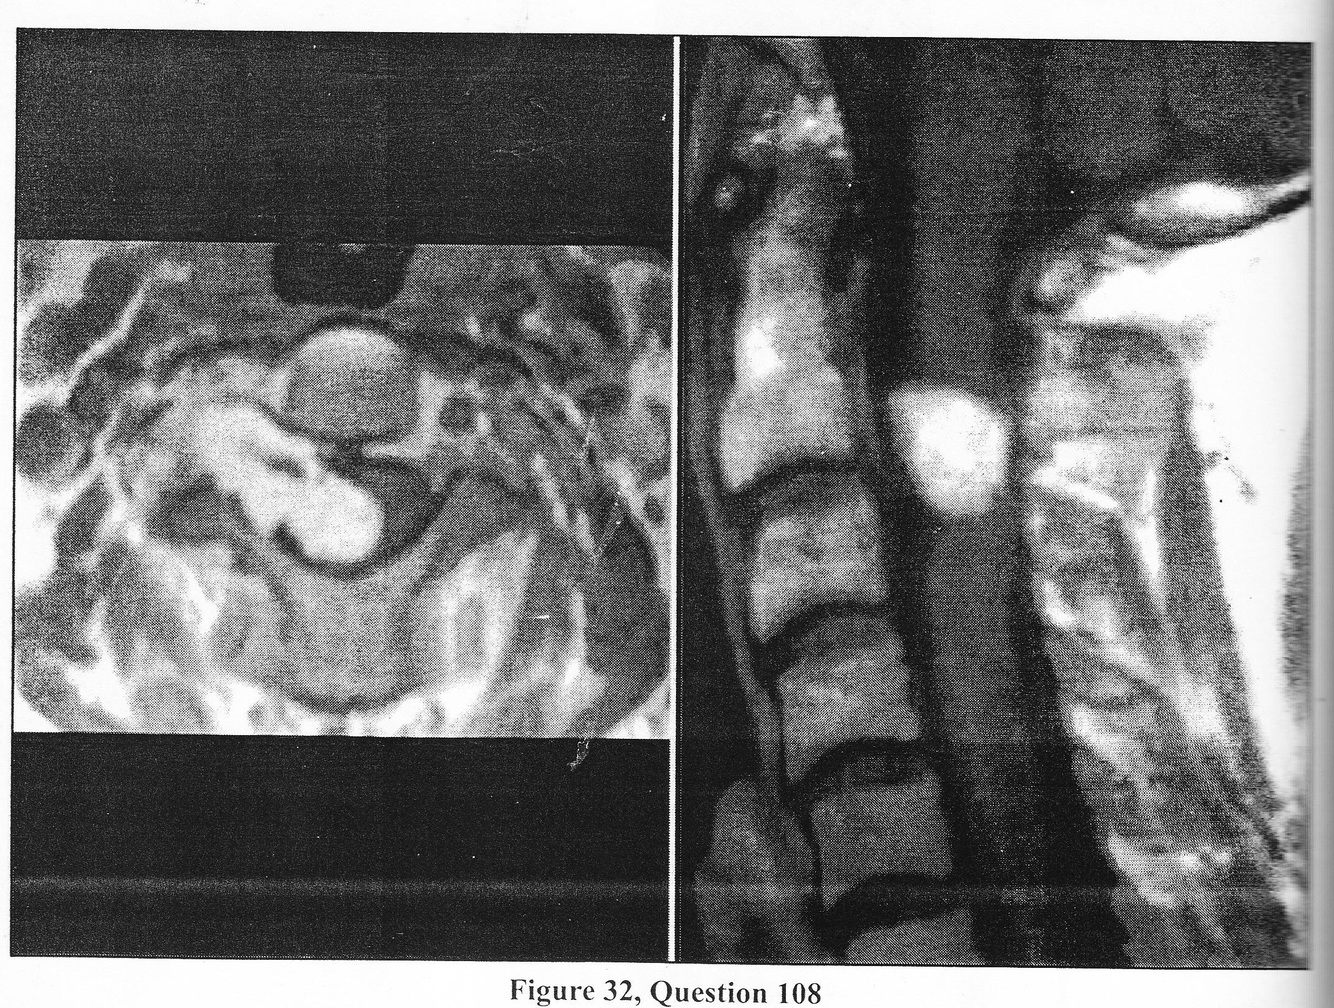

A. order a Philadelphia collar and discharge the patient home with analgesics snd muscle relaxants

B. take the patient emmergently to the OR for an occipital cervical fusion

C. place the patient in a Philadelphia collar and order an emergency myelogram

D. place the patient in a halo vest and order a CT scan of C1 and C2

E. place the patient in a halo vest and perform an emergency transoral decompression

A. prescribe analgetics for hedache/cervical pain and repeat the MRI in six months to determine if the abnormality progressing

B. perform a lumbar puncture torule out a demyelinating proscess or a metastatic or infection etiology

C. propose a transoral C2-3 vertebrectomy and resection of the mass

D. propose a right retropharyngeal approach and resection of the mass